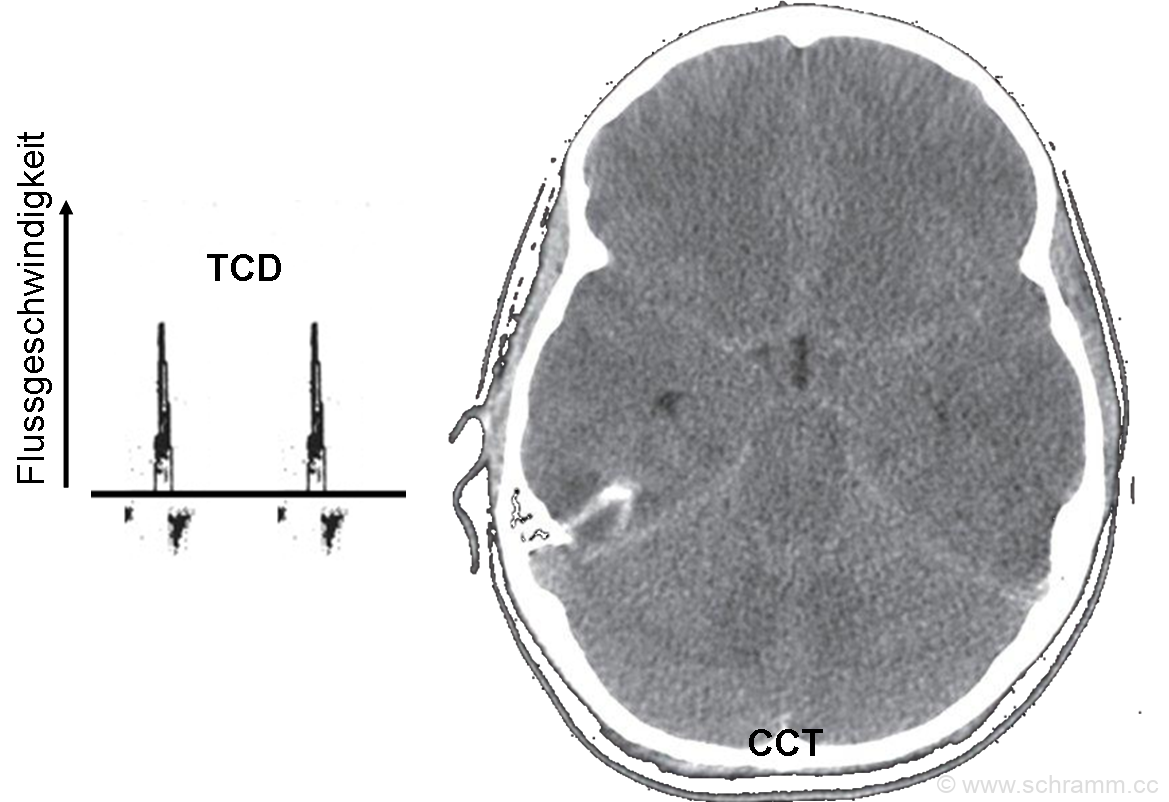

Nach der Cranialen Computertomographie (CCT) wurde eine transkranielle Doppleruntersuchung (TCD) hier der Art. cerebri media durchgeführt. Beschreiben Sie diese Bilder.

In der CCT zeigt sich ein massives Hirnödem mit Verlust der Grau-Weiß-Differenzierung.

In der TCD-Untersuchung finden sich systolischen Spikes und demnach (speziell auch in der Diastole) kein überlebensnotwendiger Blutfluss mehr, was auf einen massiv erhöhten Hirndruck hinweist.

Beide Befunde deuten auf einen Hirntod hin, zur weiteren Diagnostik wären z.B. somatosensorische (SSEP) und akustische evozierte Potentiale (AEP) indiziert.

Sollte die anschließende Hirntoddiagnostik (neurolog. Untersuchung, EEG, ...) den Hirntod verifizieren, ist dieser Patient ein potentieller Organspender.